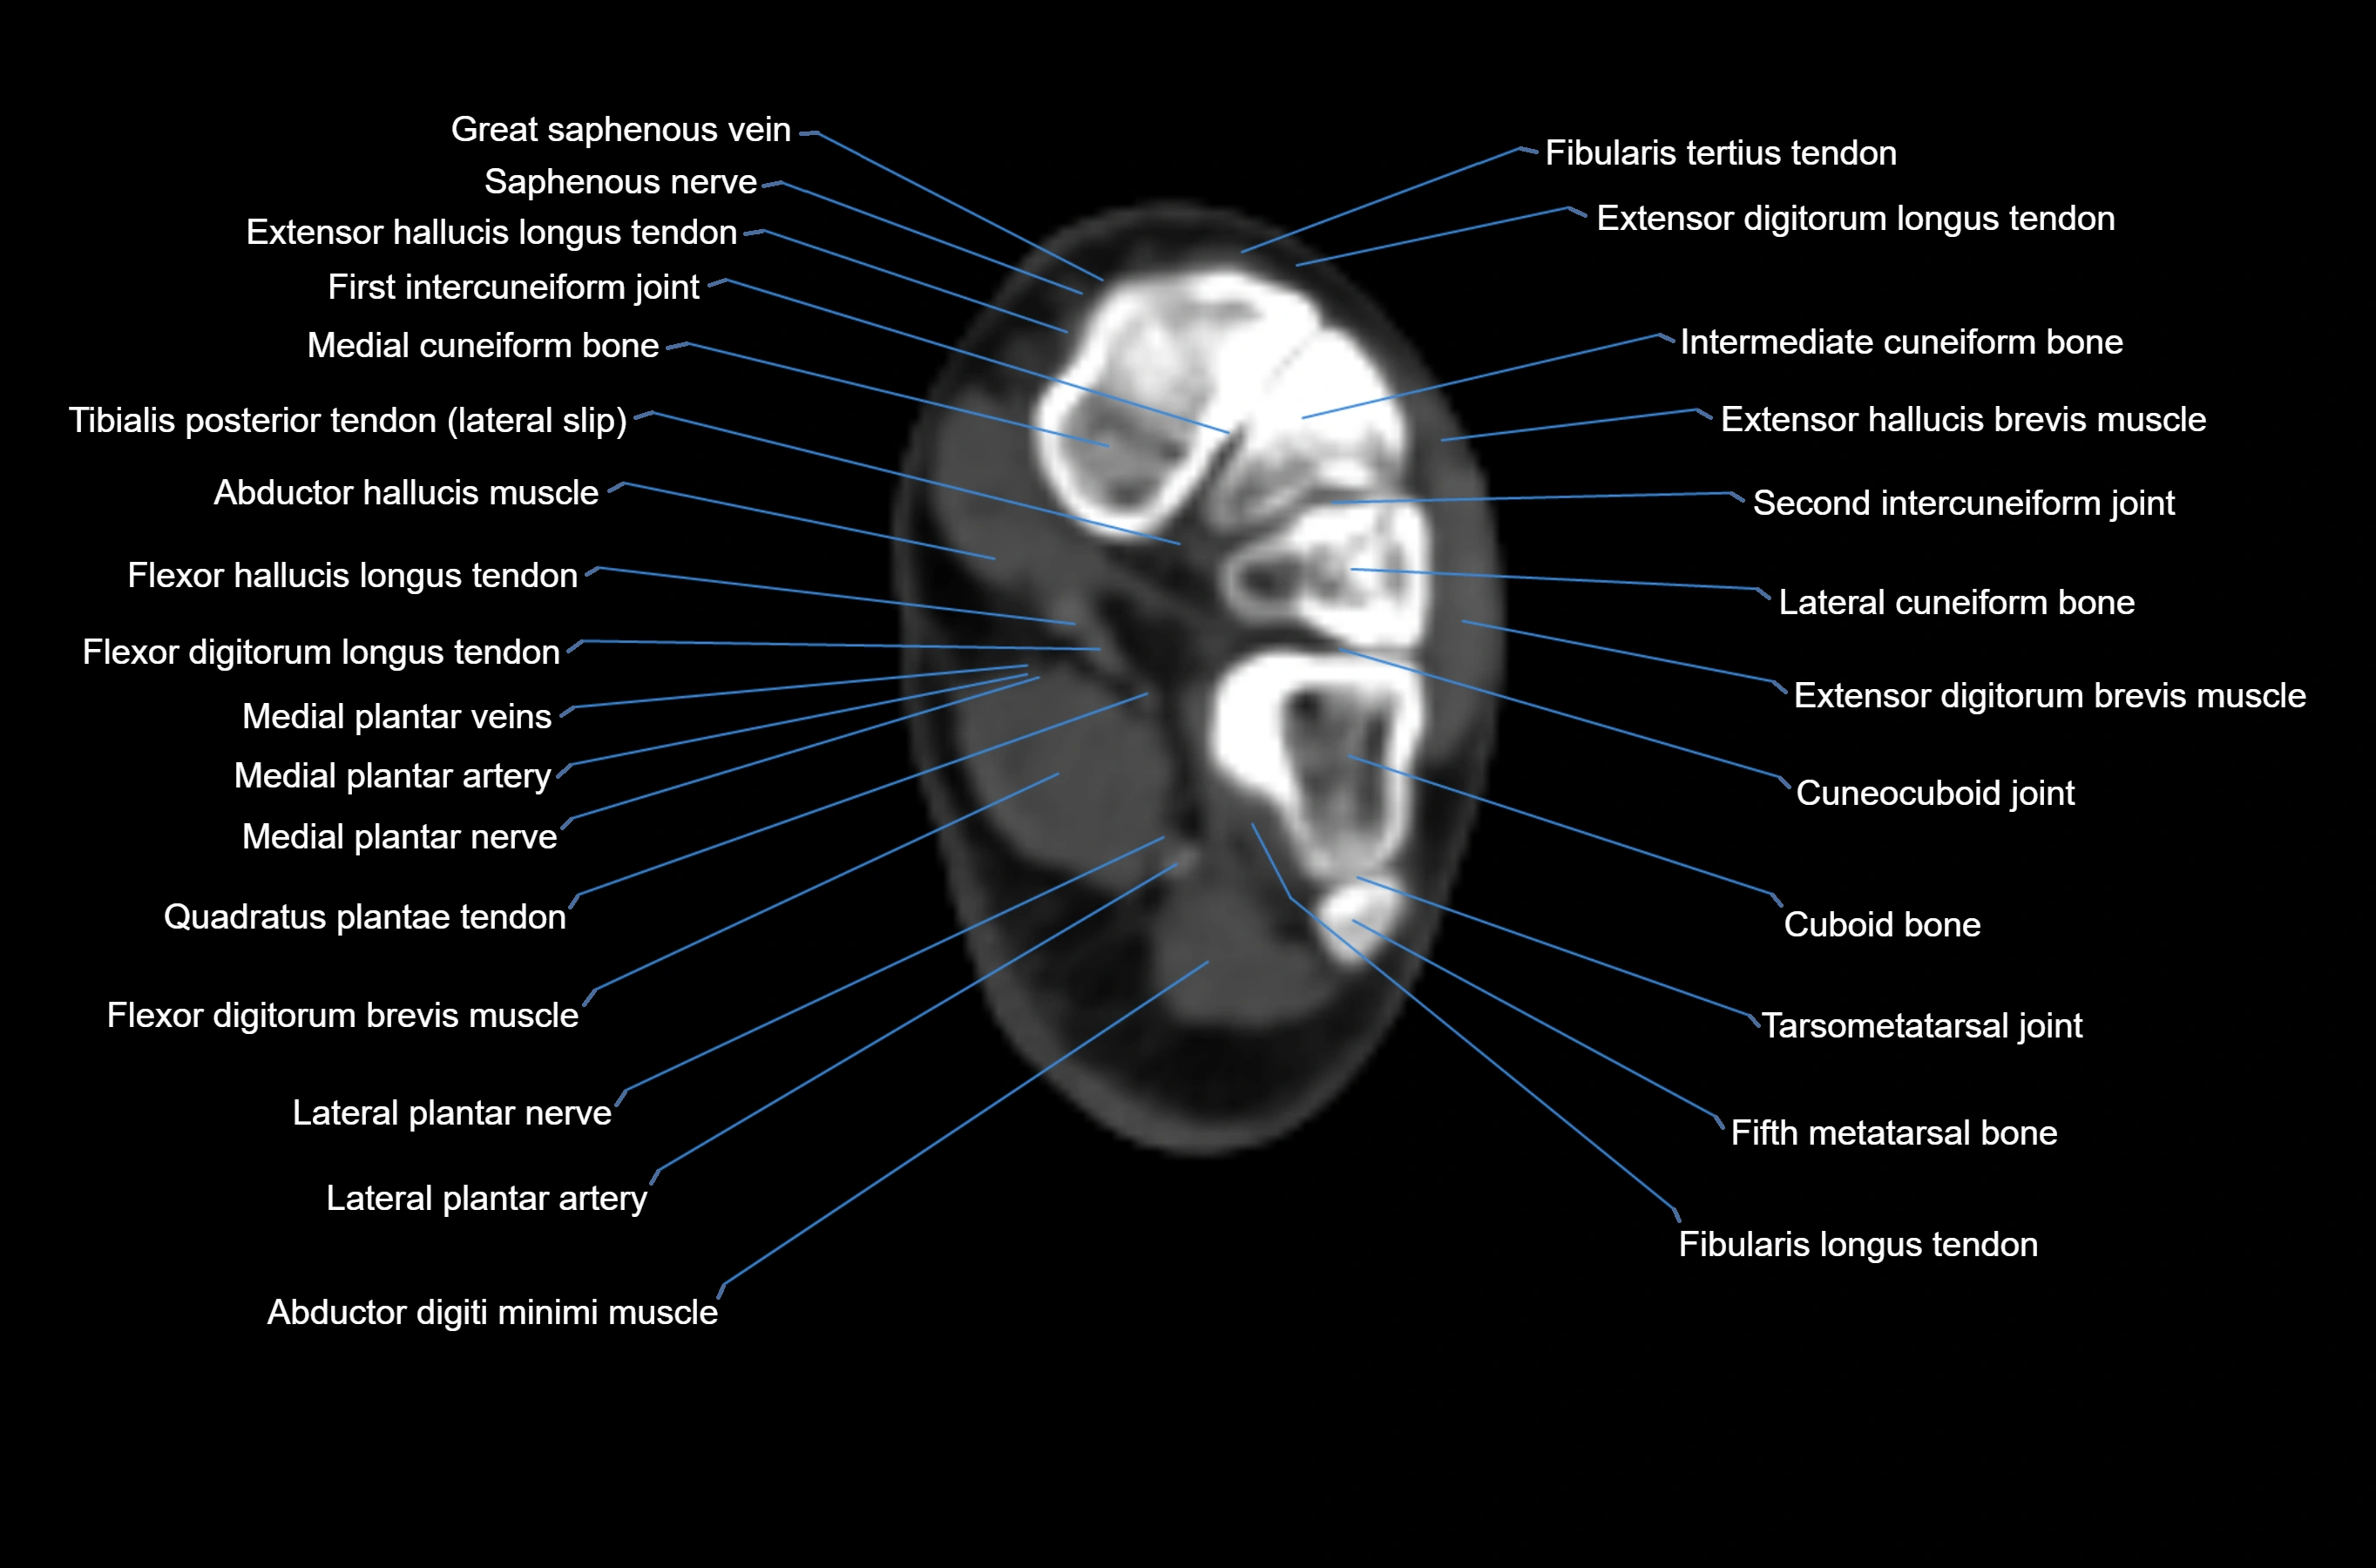

MRI image

CT image